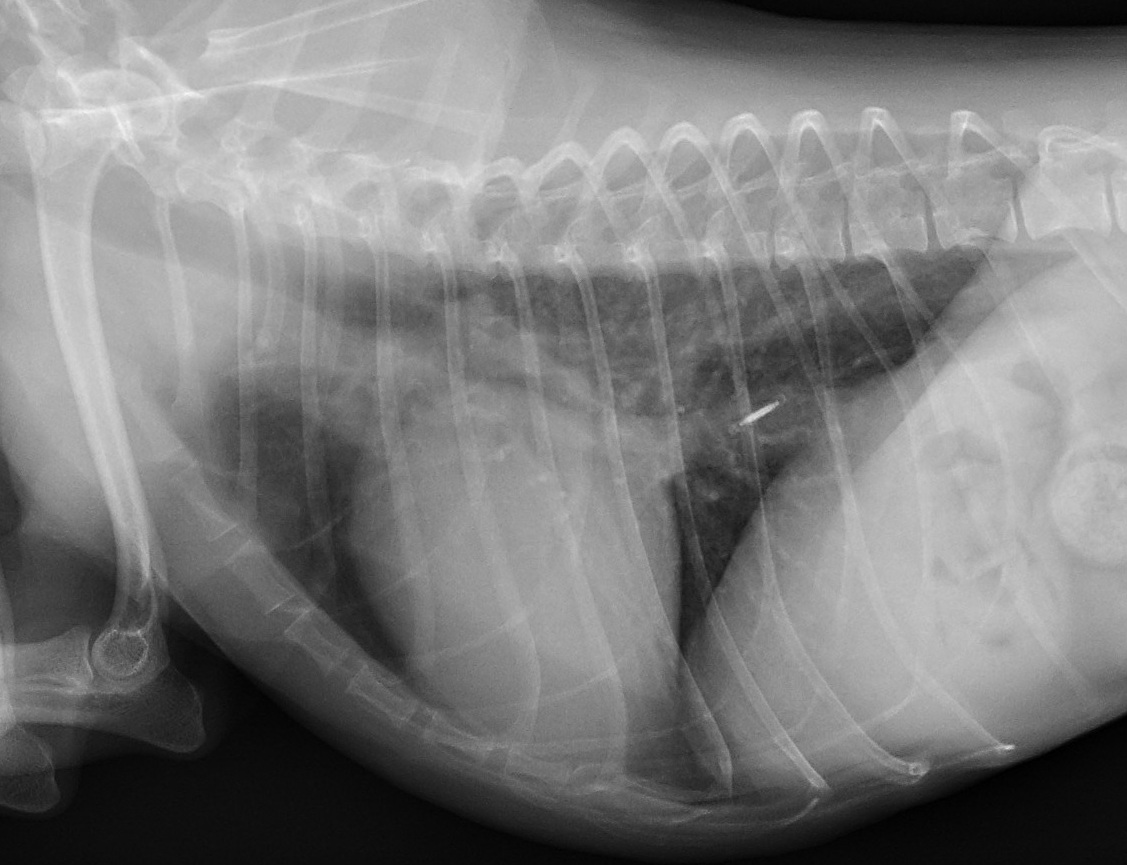

小型犬の胸のレントゲン写真です。

下が半年前のもので、

上が今回のものです。

中央に見える白くて丸い影が「心臓」です。

どうでしょう?

下の写真の心臓に比べて、

上の写真の心臓の方が大きく見えませんか?

そして、

下の心臓はまた丸みがありますが、

上の心臓は四角くなっていますよね?

これが、心拡大です。

半年での変化としては大きいように思います。